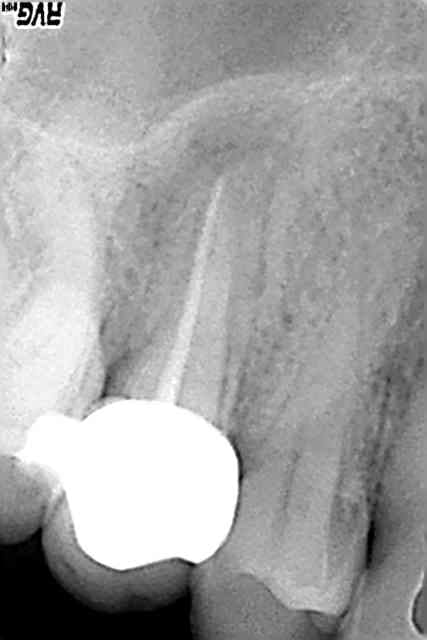

Tiens je viens de faire ça : (et quand je dis je viens, je viens. Il est 22h et la sté tourne)

Patient qui vient pour la 2eme fois avec PAA sous endo + CCM faite il y a 1 an par le gentil confrère CNSD pas cher du bled à coté. Belle pêche. Manque de bol il est parti à la retraite sans successeur. Remarque on avait à faire à un spécialiste, il a mis un cône de gutta et ça a l'air au bout sur la radio (il a explosé l'apex, j'ai obturé à 40/10ème)

Bibi il a déposé la CCM sans la péter, éliminé le moignon, refait l'endo (miracle un 2eme canal !) refait le moignon au Paracore ajusté à la CCM, scellé la CCM. Total Endo + Radio + Compo 3 faces = 97,15€

Pour moi un boulot comme ça vaut dans les 200 €.

J'aurais du faire quoi ? Penser à mon portefeuille avant tout et refaire une coiffe alors que celle ci est ajustée et date d'un an ?